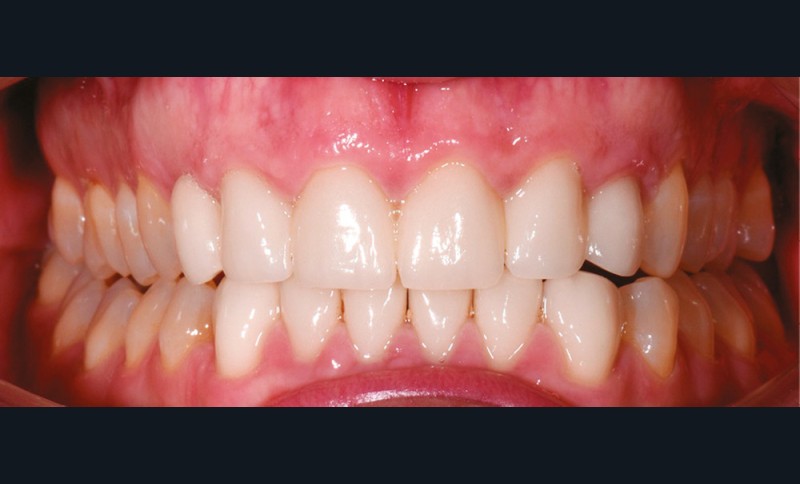

À l’examen endobuccal de première consultation (fig. 1), nous notons la présence d’un bridge maxillaire céramo-céramique sur infrastructure en zircone avec 12, 11, 21 et 22 couronnes moyens d’ancrage et 13 et 23 intermédiaires de bridge en extension. Les incisives et canines mandibulaires ont également été couronnées individuellement. Le patient nous informe que ces soins ont été réalisés pour répondre à sa demande esthétique. L’examen radiologique (fig. 2) révèle la présence de deux canines maxillaires incluses et nous montre qu’aucune dent n’a subi de traitement endodontique.